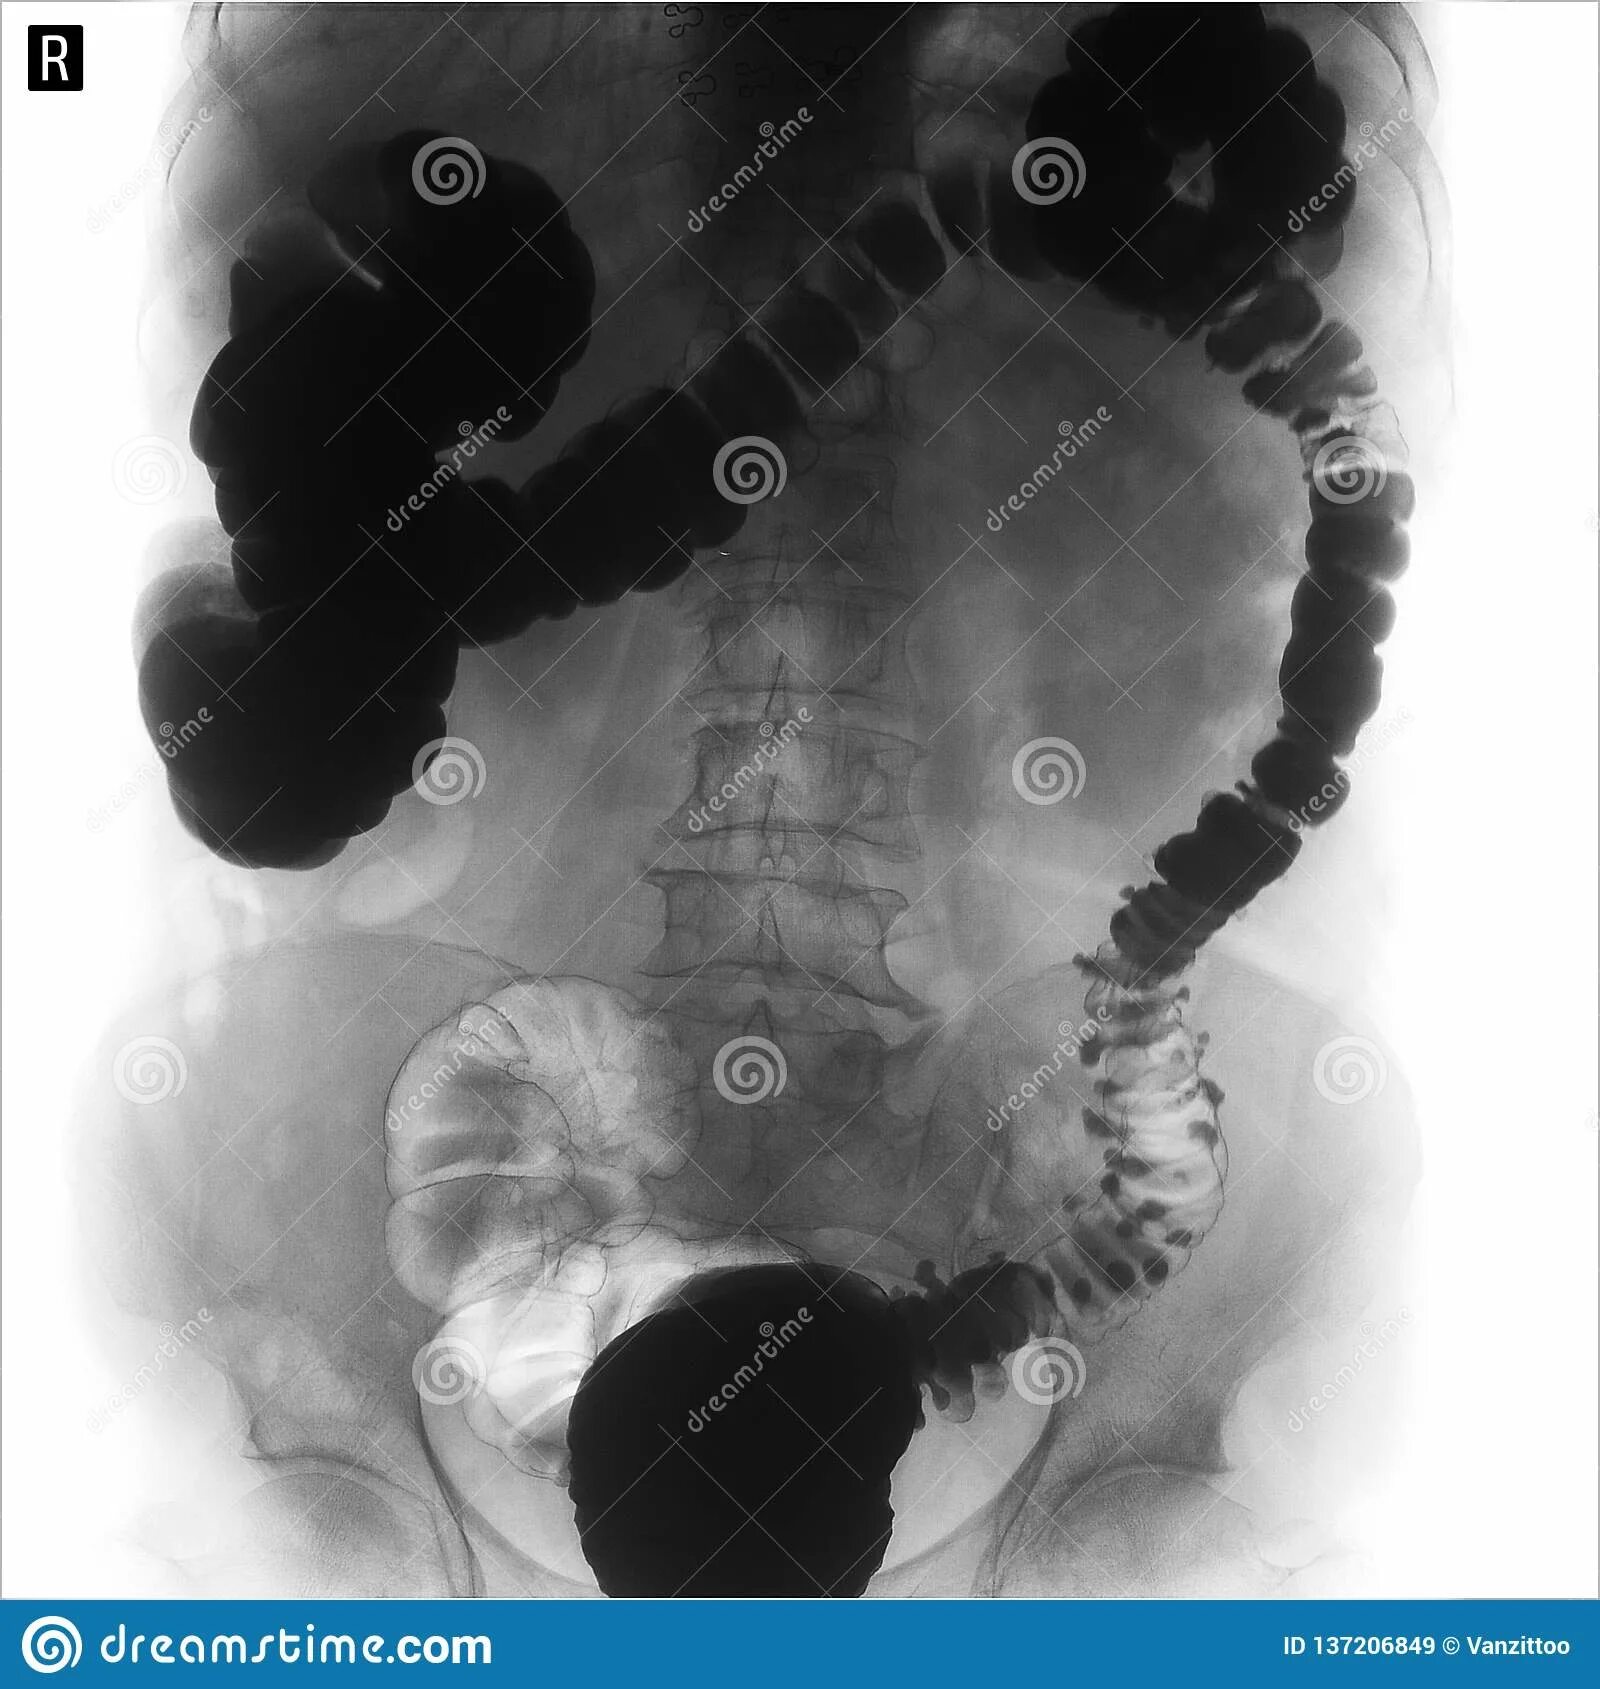

Долихоколон симптомы у взрослых